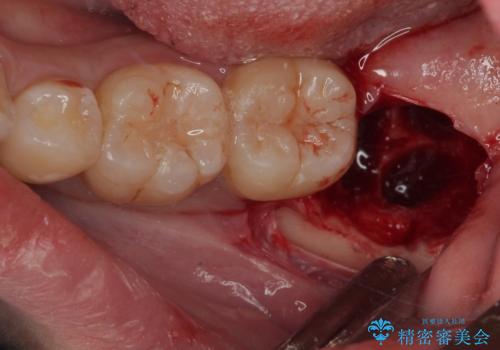

- 親知らずを抜きたいとのことで来院された患者様です。

CTで神経の位置などを確認し、抜歯術を行いました。

しっかり麻酔が効いたことを確認してから安全に抜歯を行いました。